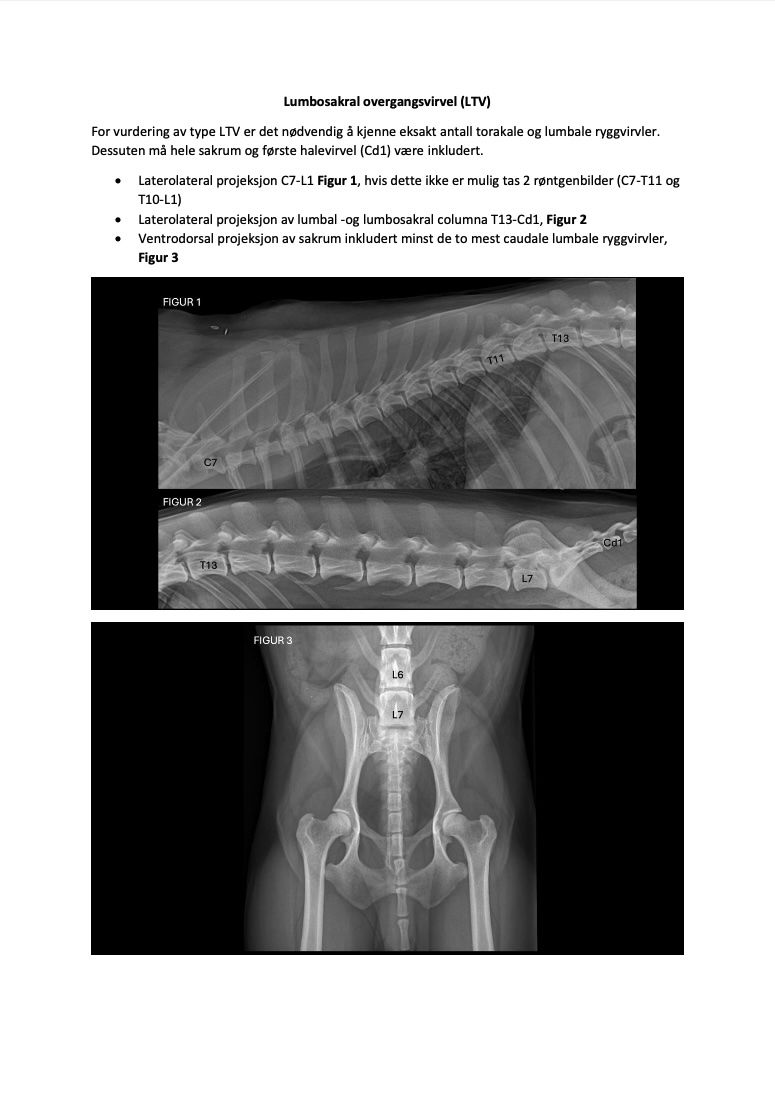

Posedyrebeskrivelse røntgen